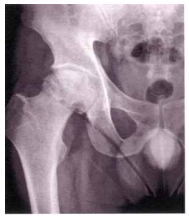

34 內傷中期治法以「和法」為基礎,《醫宗金鑑》中提到可治跌仆墮墜,閃挫損傷,合併疼痛,瘀血 凝聚等症者,是下列何種方劑? (A)正骨紫金丹 (B)獨活寄生湯 (C)蠲痺湯 (D)龍膽瀉肝湯

52 45 歲的方先生是錄影帶店的老闆,平日有酗酒習慣約 20 年, 但無重大外傷,右髖隱隱作痛已經 3 年,盤坐時或劇烈運動後 疼痛加劇,至醫院檢查其 X 光如右圖,其診斷為何? (A)缺血性骨壞死 (B)骨結核 (C)骨腫瘤 (D)痛風性關節炎